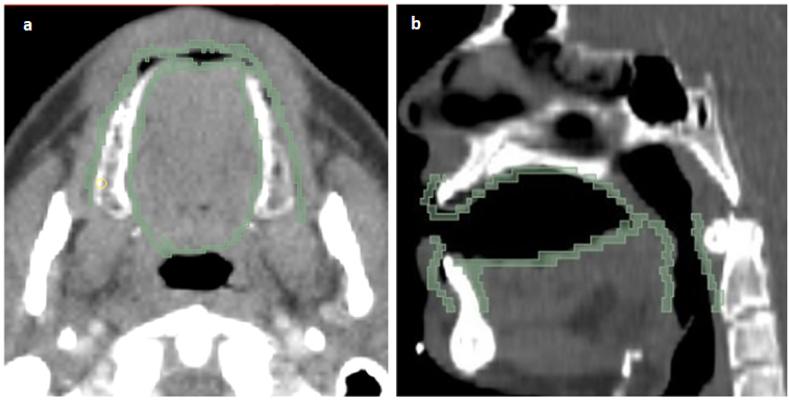

In this single-center prospective study, 49 HNCs treated with curative intensity modulated radiotherapy (IMRT) were enrolled. Baseline CT images ( CT simulation), dosimetric, and clinical features were collected. RIOM was assessed using CTCAE v.5.0. RFs were extracted from manually-contoured oral mucosa structures. Minimum-redundancy-maximum-relevance (mRMR) method was applied to select the most informative radiomics, dosimetric, and clinical features. Then, binary prediction models were constructed for predicting acute RIOM based on the top mRMR-ranked radiomics, dosimetric, and clinical features alone or in combination, using random forest classifier algorithm. The predictive performance of models was assessed using the area under the receiver operating curve (AUC), accuracy, weighted-average based sensitivity, precision, and F1-measure.

方法